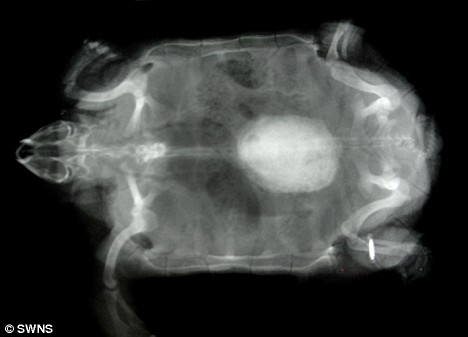

X光顯示波莉體內(nèi)的結(jié)石

獸醫(yī)組負(fù)責(zé)人莎倫·雷德羅塞介紹說,獸醫(yī)日前為園內(nèi)的動物做了例行體檢,當(dāng)用X光照一只名叫波莉的雌性非洲餅干龜時,醫(yī)生們驚奇地發(fā)現(xiàn)它體內(nèi)竟然有一個雞蛋大小的東西,而5歲大的波莉身長才不過5.5英寸(約合14厘米)!

雷德羅塞表示,如果不取出波莉體內(nèi)碩大的結(jié)石,它最終將因腎衰竭而死去。給龜實(shí)施麻醉非常具有挑戰(zhàn)性,必須受過專門訓(xùn)練的獸醫(yī)才能進(jìn)行,但是鑒于波莉已經(jīng)出現(xiàn)不適,動物園的獸醫(yī)還是決定盡快去除它體內(nèi)的結(jié)石。手術(shù)共進(jìn)行了一個小時,獸醫(yī)先是在波莉腹部的殼上切開一個洞,然后取出結(jié)石,最后再把切開的殼粘合起來。取出的結(jié)石重19克,大小為1.5英寸×1.2英寸(約合4厘米×3厘米)。據(jù)分析,這塊結(jié)石是波莉體內(nèi)的鈣沉積形成的。